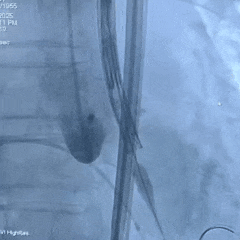

手术过程

根部造影:可见瓣叶钙化,几乎无反流

20mm球囊扩张,无腰,球囊轻微滑动

瓣膜系统定位

瓣膜展开后造影评估,深度可,无明显瓣周漏

多角度造影评估:瓣膜深度形态合适,冠脉灌注良好

脱钩后造影:瓣膜无位移,同轴性良好,无瓣周漏

术后超声测量

即刻瓣口流速2.2m/s;平均压差9mmHg,手术结束